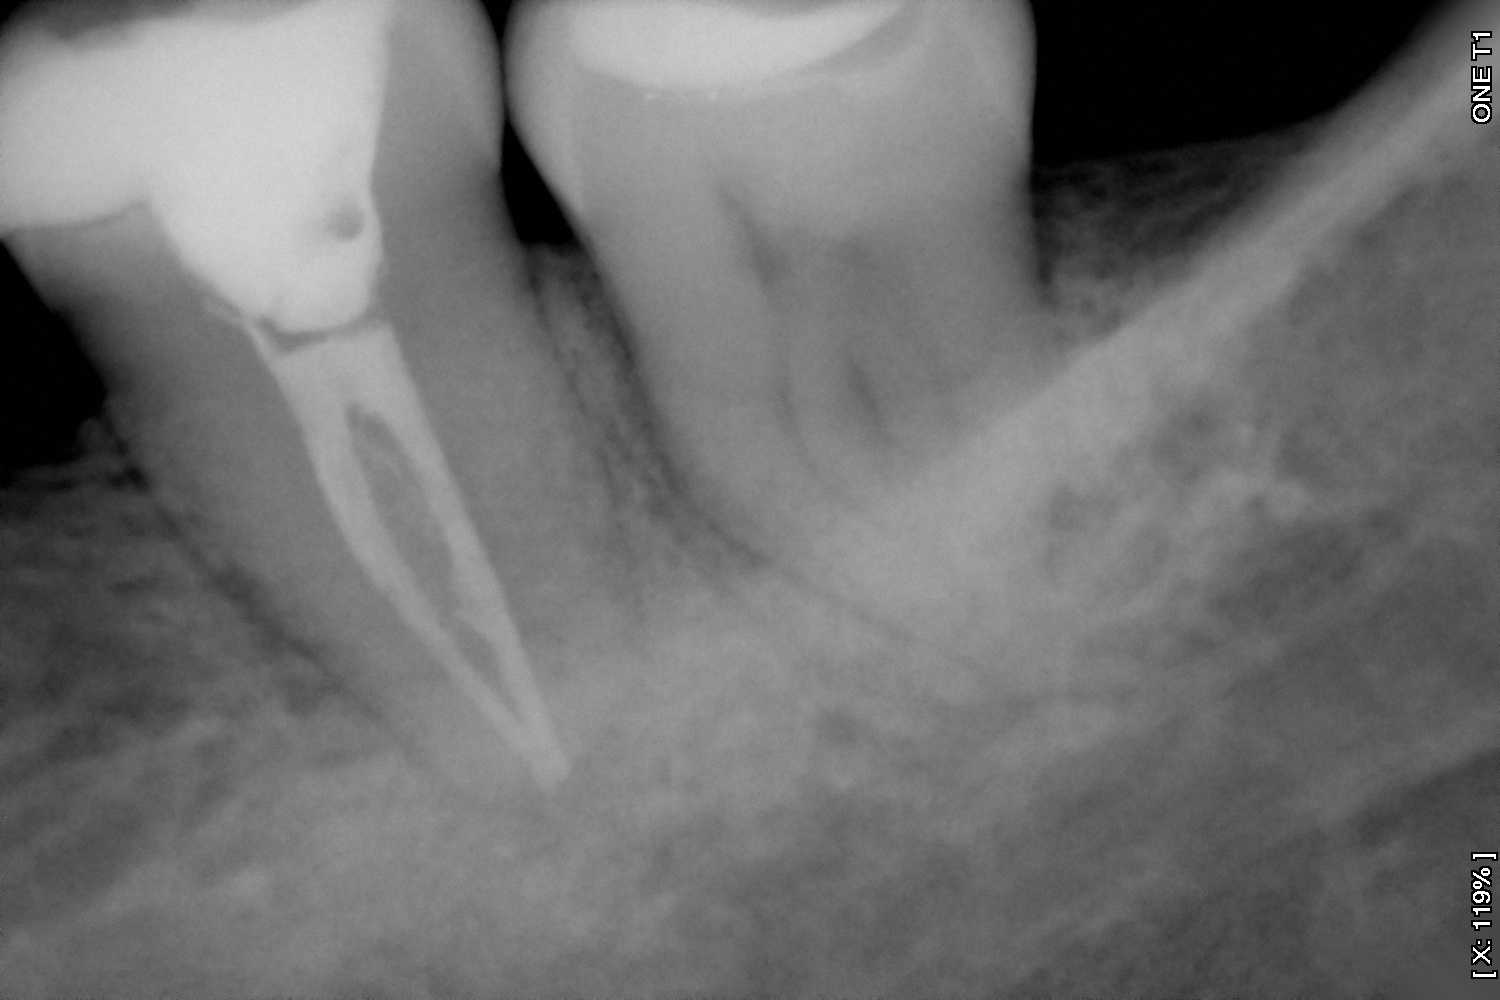

Es la especialidad que se encarga de retirar el nervio del diente cuando éste ha sido afectado por una caries, por un golpe o simplemente por requerimiento de un procedimiento de rehabilitación que esté causando sintomatología.

Y en DentPro realizamos tratamientos endodónticos con la más avanzada tecnología, utilizando sistemas rotatorios y radiografías digitales.